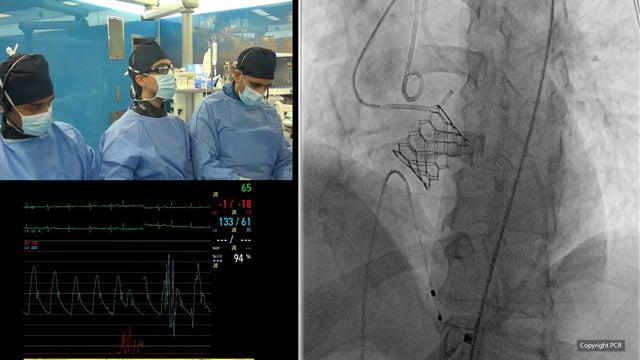

Mitral transcatheter edge-to-edge repair - LIVE Case

29 Sep 2025 – From PCR Gulf Valves 2025

This live educational session from Prince Sultan Cardiac Center in Riyadh offers an in-depth look at mitral transcatheter edge-to-edge repair (TEER) with MitraClip. Learn best practices for patient selection, imaging analysis, operator strategies, and witness a live case procedure to optimize clinical outcomes.

LIVE Educational Case from...